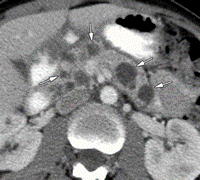

- Kontrastlı KT və ya MRT standart müayinədir, şişi və yayılma dərəcəsini müəyyənləşdirilməsində önəmlidir.

- Görüntüləmdə: erkən arterial fazada contrast tutan və venoz fazada yuyulan, MRT-də hipointens, ətraf toxumalara invaziv, böyüməyə meylli, baş nahiyyəsində yerləşərək xoledoxu və pankreatik axacağı genişləndirən (“iki axacaq simptomu”) törəmə

- Kontrastlı KT/MRT (5 mm-lik kəsiklərlə aparılan kontrastlı KT/MRT 50 – 60% həssaslıq göstərir.

- Kontrastlı KT və ya MRT ilə pankreasda kütlə təyin İnsulinomalardan fərqli olaraq qlükaqonomalar böyük ölçülü olurlar və tapılması çətinlik törətmir. Adətən cisim və quyruq nahiyyəsində yerləşirlər.